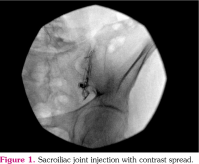

From our clinical observations, we notice that pain relief occurs after sacroiliac joint steroid injection in patients diagnosed with active sacroiliitis. We suppose that these injections provide pain relief apart from the NSAIDs. Moreover, we are in the opinion that NSAID usage and corresponded complications may decrease after reducing the pain. Therefore, in addition to prescribing NSAIDs in the PM&R clinic as the main treatment, we pain specialists also recommend sacroiliac joint steroid injections to patients at baseline. Nevertheless, we inform the patients about the details though it is a minimally invasive procedure and allow them to decide on whether or not to undergo the intervention. Fluoroscopy-guided sacroiliac joint steroid injections are performed in our clinic by a pain management specialist with more than 10 years of experience. These patients are placed in the prone position; skin is wiped three times with a povidone-iodine solution and covered with sterile covers. The C-arm is angled 25-35 degrees caudally from the axial plane on average and with 0-30 degrees medial oblique rotation so as to clearly visualize the posteroinferior angle of the sacroiliac joint. After the joint is displayed, the needle insertion point in the inferior section, which is the synovial part, is determined. Local anesthesia is performed with 3 mL of prilocaine. After capturing an image in the coaxial plane according to the X-ray direction, a 22G, 3.5-inch spinal needle is advanced and inserted into the sacroiliac joint under intermittent fluoroscopy, and intra-articular placement is confirmed by injecting 0.5 mL of iohexol (Figure 1). Half of the mixture of 80 mg of triamcinolone acetonide and 1 mL of 0.5% bupivacaine is administered, and than the same procedure is applied to the other sacroiliac joint. Patients without complications are discharged and advised to attend follow-up visits.